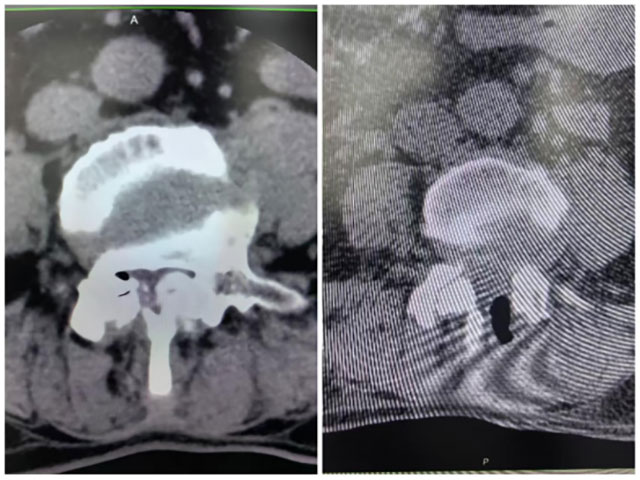

重度腰椎椎管狭窄合并黄韧带骨化

腰椎椎管本是脊髓神经的“保护通道”,可随着年龄增长或长期劳损,这个通道会慢慢变窄,椎管后方的黄韧带还会钙化、骨化,变成坚硬的“小石块”死死压迫神经,当狭窄程度超50%,各种难忍的症状便会找上门。

61岁的王女士腰腿痛5年,最严重时走50米就得蹲下,双下肢麻木胀痛,辗转多家医院保守治疗都无效。来到西南医科大学附属中医医院骨伤科脊柱·肿瘤一组,确诊为重度椎管狭窄合并黄韧带骨化。团队为她定制了UBE微创手术方案,术后剧痛明显缓解,3天后就能下床慢走,双下肢的麻木胀痛感彻底消失。随访半年,王女士每天买菜、跳广场舞样样都行,逢人就说:“我终于又能好好走路了!”